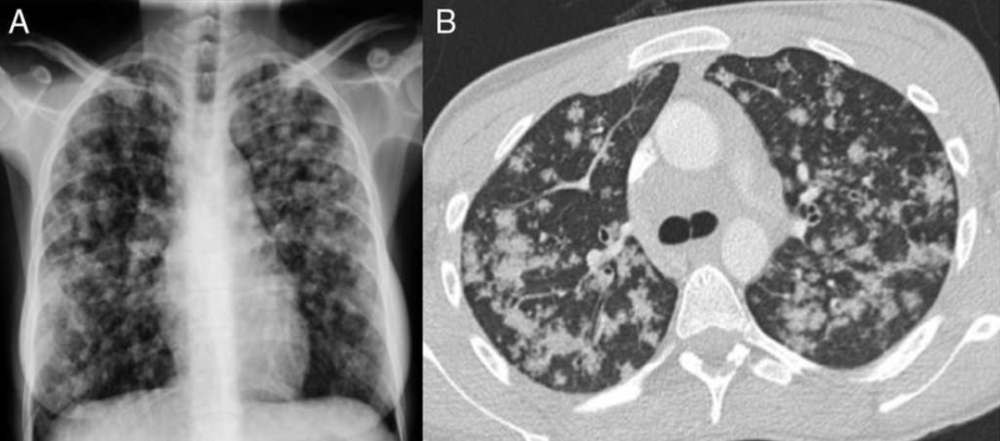

血行播散性肺结核的影像表现及鉴别诊断影像天地

如果说是血行播散,这些病变比一般的粟粒性肺结核又显然粗大的多

血行播散型肺结核Ⅱ型(图3-24,3-25)大量结核菌一次或短期内多次